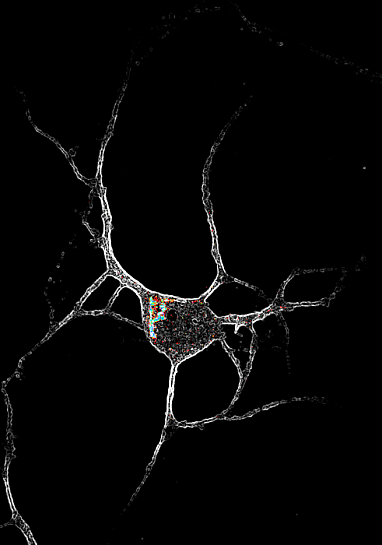

Picture of Brain cell with effect of psychedelics

Brain Science: We have discussed the promise of psychedelics in treating bipolar and depression health issues. The February issue of "The Scientist" magazine outlined clinical studies that discovered that hallucinogenic drugs slip past cell membranes and bind brain cells. Without trying to get into the brain receptors discussion again let's just let it be said that we have definitely found the classification of the inner brain cells related to positive feelings and thought. Also they have found that brain cell neurotransmitters (serotonin) are affected by psychedelics to the extent that they smooth out the reactions across the brain cells. ( you may recall that neurotransmitters are connecting fluids between cells.) They can either inhibit conductivity or promote it. Thus if we can control the conductivity of cells associated with depression and bipolar reactions then we can control both. What is also interesting from February's report ,is that that in affecting the neurotransmitter (serotonin), the drugs also affected the coating of the nerve brain cell stem by making it more, for lack of a better term, more greasy. Whats that mean? It "slikens" the brain cell stem so that it produces more dendrites (connecting points) and produce a more plastic brain. In other words, it promotes new brain cell growth and connections. That gives us a clue as to why more positive behavior may result from psychedelics. If the drug is coupled with the right exterior inputs we can create new learned positive behavior in the patient's brain. ( Now at this point I think this gets a little scarey... will talk about that in "So What".) So what we are looking at now is that psychedelic drugs my not only repress negative reactions in the brain it also may facilitate and create improved behavior. Wouldn't that be amazing!